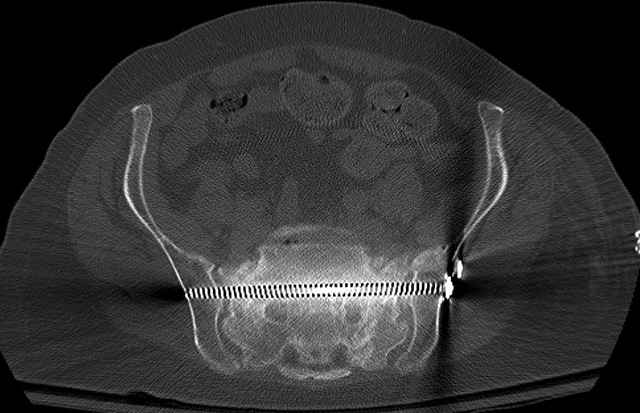

Pelvic CT Scan - 3 Months After Fall

Ramus Fractures

Percutaneous Fixation

(B) Ramus-Retrograde

2 TransIliac-TransSacral